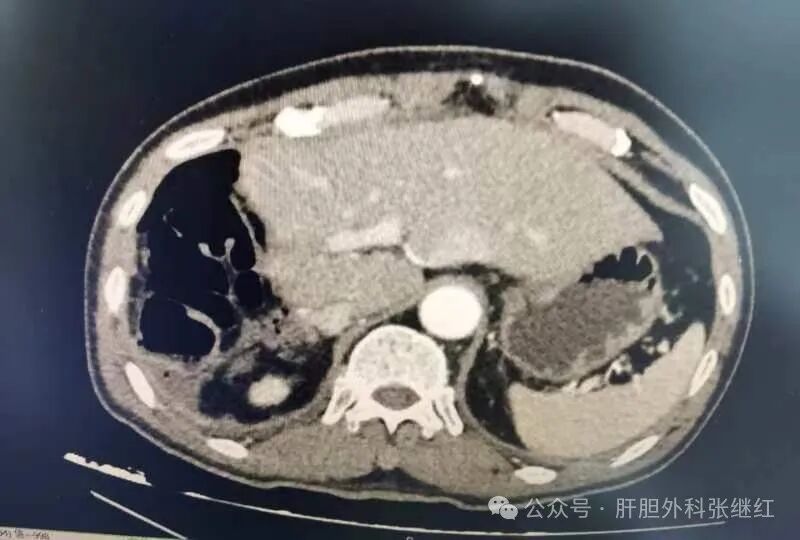

add68c8af7a4483b91a16add39e28962.jpg

靶向免疫治疗3个疗程后CT